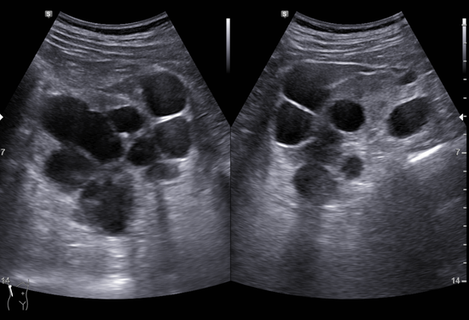

다낭성 신질환 2

70대 남자

협심증으로 투약 중

이전에 신낭종에 대한 흡인술 수차례

Cr 1.7, 혈압은 정상

초음파 소견